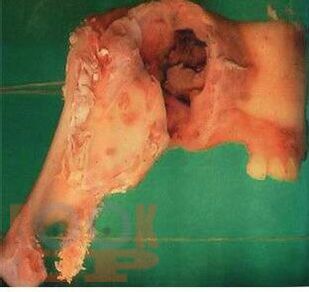

Ce manuel a été élaboré conformément au programme de travail «Anatomie pathologique» et est destiné au développement des compétences professionnelles des étudiants de 2e année de la Faculté de médecine dentaire dans la discipline «Anatomie pathologique» dans la spécialité 31.05.03 Dentisterie. Le manuel comprend plusieurs chapitres, dont une description de la structure normale et de l'anatomie pathologique des maladies des organes dentaires en français. Le manuel est équipé d'un grand nombre de photographies, le matériel est présenté à un niveau théorique moderne.

Данное учебное пособие разработано в соответствии с рабочей программой «Патологическая анатомия» и предназначено для освоения профессиональных компетенций студентами 2 курса стоматологического факультета по дисциплине «Патологическая анатомия» по специальности 31.05.03 Стоматология. Учебное пособие состоит из нескольких глав, включая описание нормального строения и патологической анатомии заболеваний органов зубочелюстной области на французском языке.

Пособие оснащено большим количеством фотографий, материал излагается на современном теоретическом уровне.